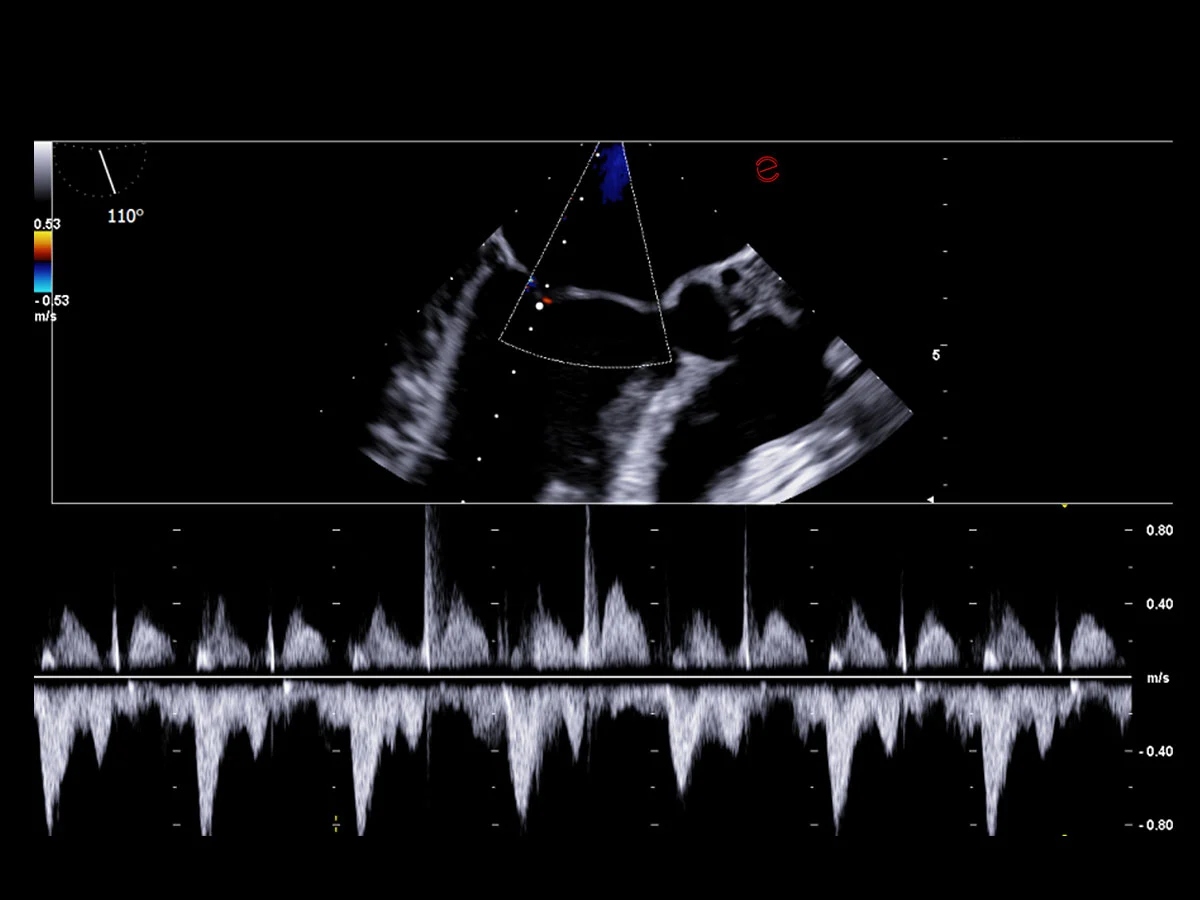

Innovative hemodynamic assessment with HyperDoppler

Esaote’s HyperDoppler technology provides an advanced visualization of intracardiac blood flow dynamics, offering clinicians an intuitive understanding of complex hemodynamics that goes beyond conventional Doppler imaging. By generating real-time vector maps, streamlines, and vortex formations, HyperDoppler enables the detailed assessment of diastolic function, ventricular dyssynchrony, and valvular abnormalities.

This unique flow visualization supports earlier detection of subtle dysfunction and increases diagnostic confidence, particularly in challenging cases such as heart failure, prosthetic valve evaluation, and structural heart disease. HyperDoppler’s zero-click, visually rich interface enables faster, more comprehensive exams, allowing cardiologists to make more informed clinical decisions.